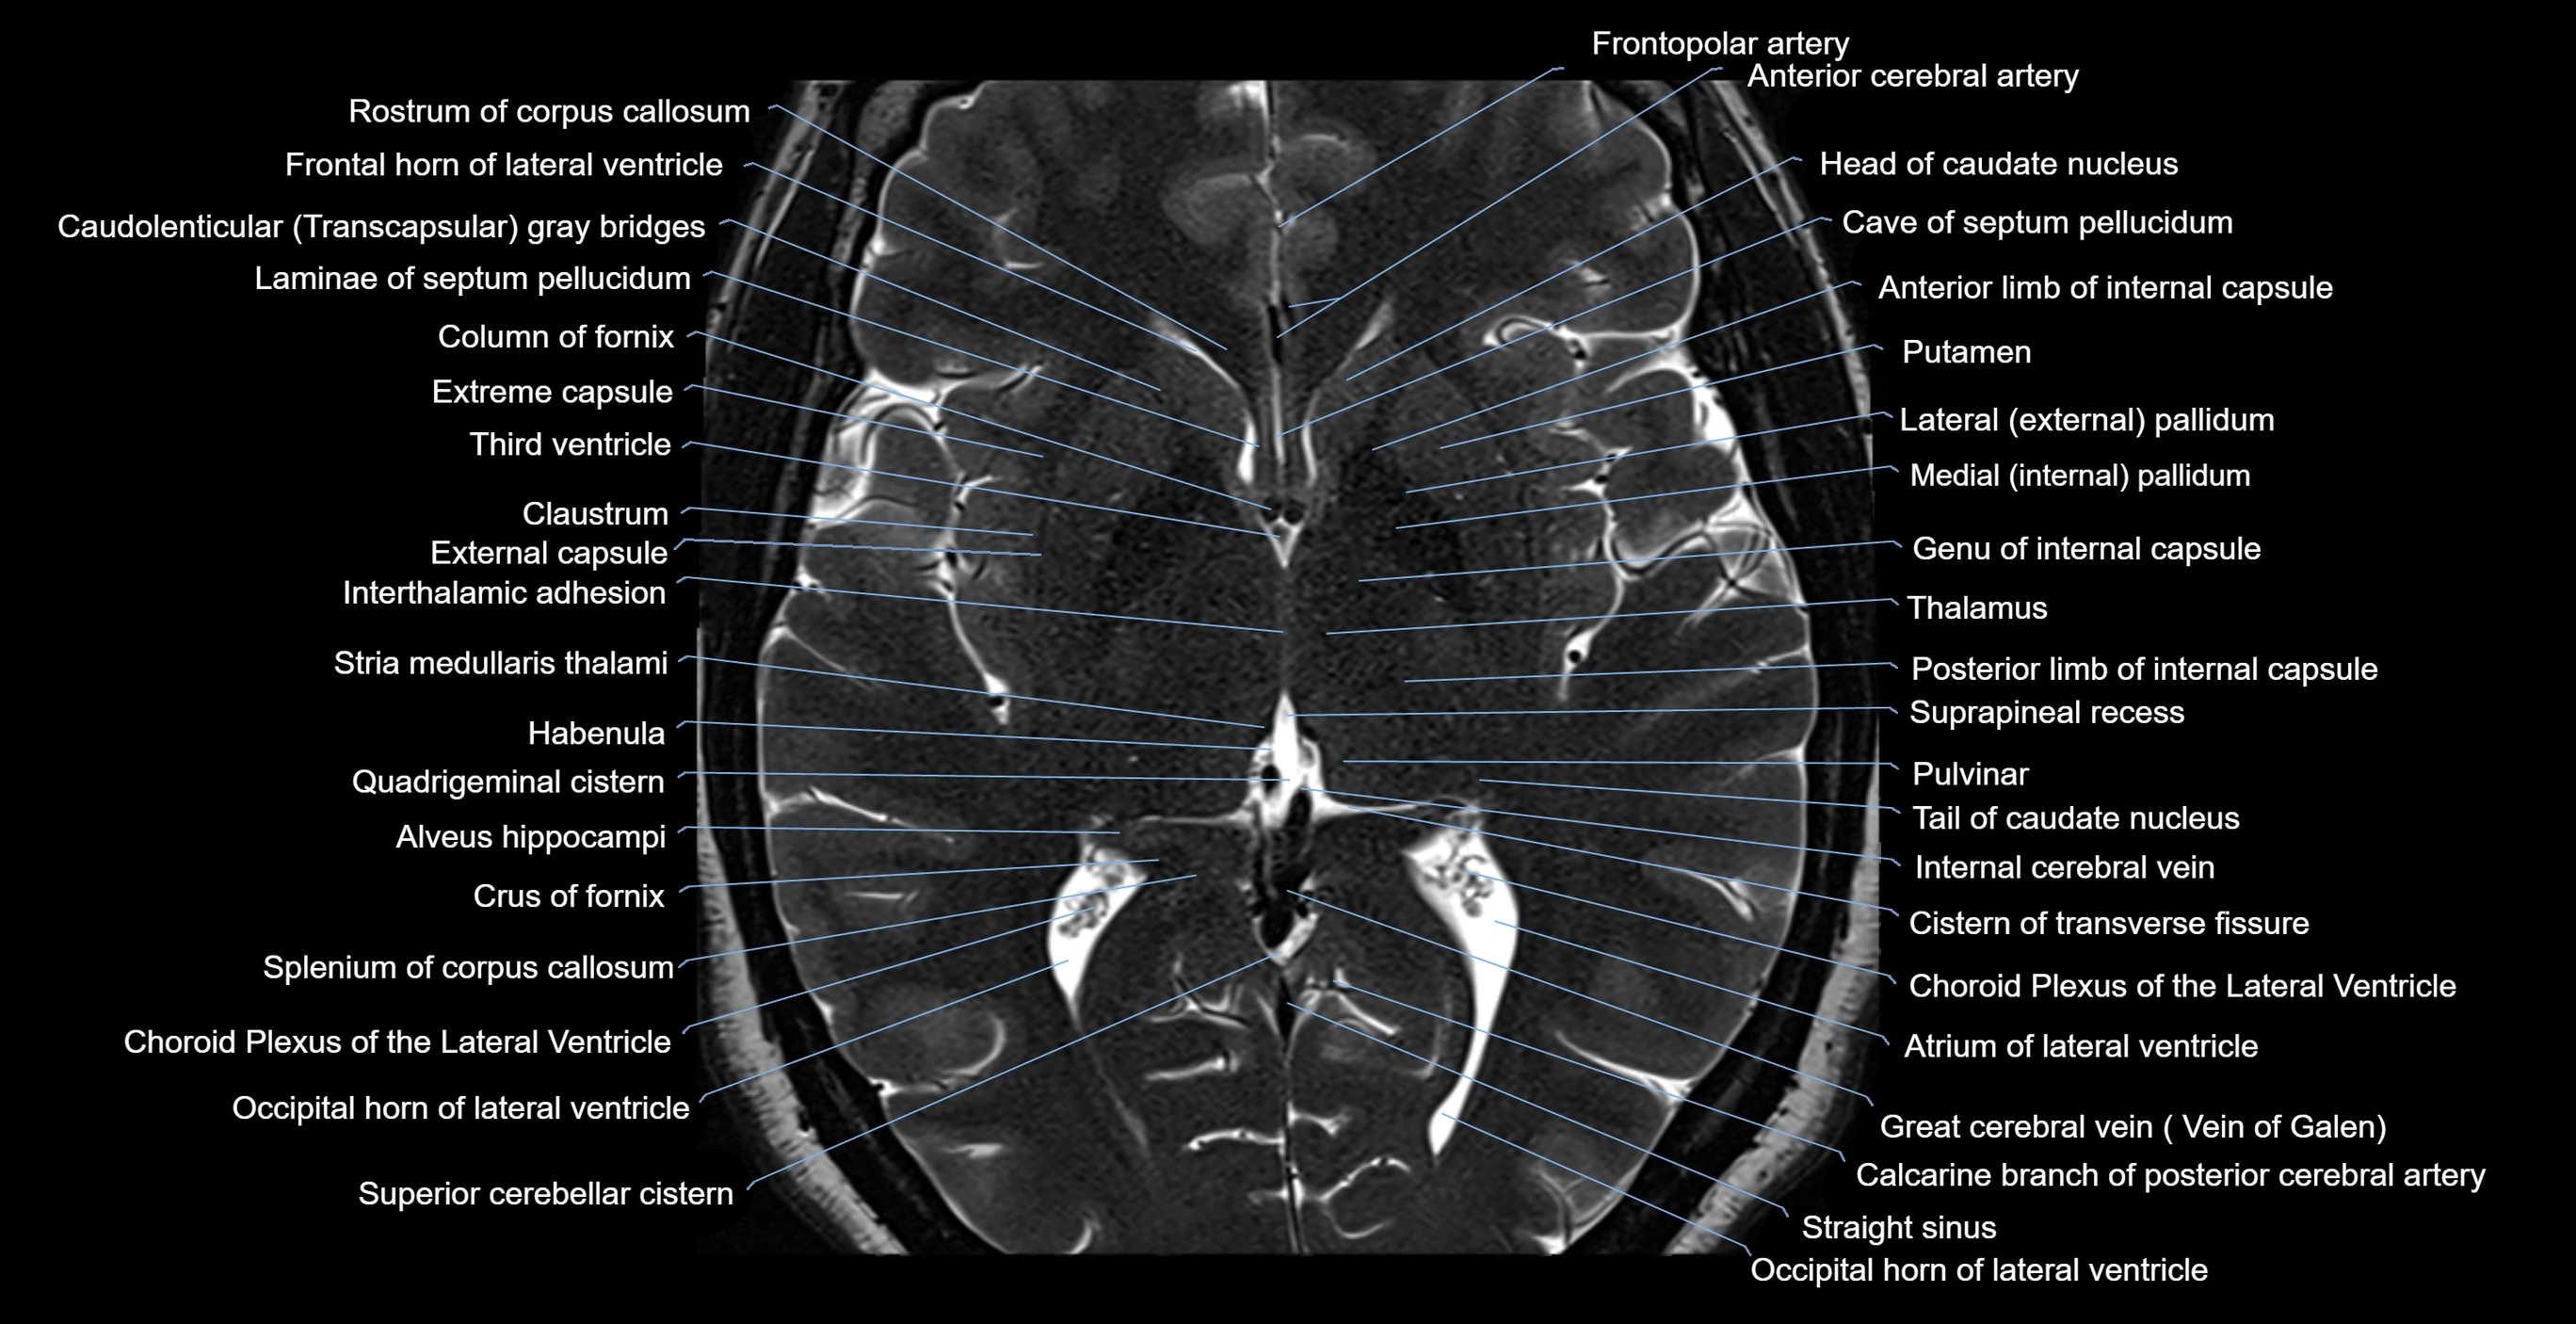

- Atrium of lateral ventricle

- Body of caudate nucleus

- Body of fornix

- Cave of septum pellucidum

- Claustrum

- Column of fornix

- Crus of fornix

- External capsule

- Extreme capsule

- Frontal horn of lateral ventricle

- Great cerebral vein

- Habenula

- Internal cerebral vein

- Interthalamic adhesion

- Occipital horn of lateral ventricle

- Posterior limb of internal capsule

- Pulvinar

- Putamen

- Quadrigeminal cistern

- Rostrum of corpus callosum

- Septum pellucidum

- Splenium of corpus callosum

- Straight sinus

- Stria medullaris thalami

- Suprapineal recess

- Tail of caudate nucleus

- Tela choroidea of third ventricle

- Temporal horn of lateral ventricle

- Third ventricle